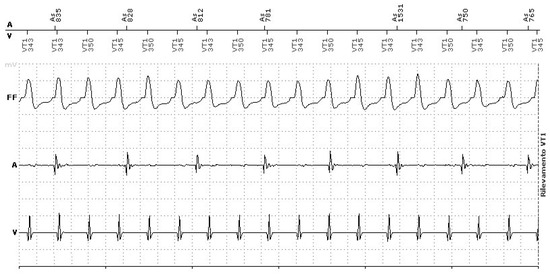

3.1.1. Endless Loop Tachycardia (ELT)

- Crea, P.; Picciolo, G.; Crea, T.; Luzza, F. Spike on T wave! What went wrong? J. Electrocardiol. 2017, 50, 139–141. [Google Scholar] [CrossRef]

- Crea, P.; Crea, T.; Picciolo, G.; Luzza, F. SafeR and escape junctional rhythm: A singular trigger for pacemaker-mediated tachycardia. J. Electrocardiol. 2017, 50, 504–506. [Google Scholar] [CrossRef] [PubMed]

- Savio, A.L.; Crea, B.; Dattilo, G.; Crea, P. Risks of inappropriate use of an algorithm favouring intrinsic conduction. Pacing Clin. Electrophysiol. 2022, 45, 1345–1348. [Google Scholar] [CrossRef]

- Frumin, H.; Furman, S. Endless loop tachycardia started by an atrial premature complex in a patient with a dual chamber pacemaker. J. Am. Coll. Cardiol. 1985, 5, 707–710. [Google Scholar] [CrossRef] [PubMed]

- Strik, M.; Frontera, A.; Eschalier, R.; Defaye, P.; Mondoly, P.; Ritter, P.; Haïssaguerre, M.; Ploux, S.; Bordachar, P. Accuracy of the pacemaker-mediated tachycardia algorithm in Boston Scientific devices. J. Electrocardiol. 2016, 49, 522–529. [Google Scholar] [CrossRef] [PubMed]